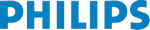

Киста молочной железы, датчик L12-5